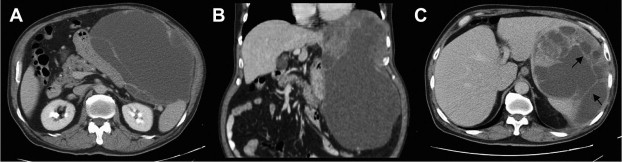

A 63-year-old male patient was admitted to our hospital due to a palpable solid mass with left upper quadrant abdominal pain for 4 months. He has no past history of Hepatitis B virus (HBV) or Hepatitis C virus (HCV) infection. Otherwise, he lost 10 kg of body weight within 8 months. Laboratory studies showed no elevation of liver function, alkaline phosphatase, and bilirubin. Abdominal ultrasonography showed a heterogeneous mass in the intra-abdomen, which was about 10 cm in diameter, with a peripheral cystic-like component near there about 13 cm in diameter. Abdominal computed tomography (CT) showed a huge well-circumscribed mass at left upper quadrant, up to 21.3 × 13 × 27.9 cm3 in size, seemed to have arisen from the gastric fundus (Fig. 1A and B), Much inner nonenhancing low-density collection, with enhancing soft parts, punctuate calcifications, and multiple septum in delayed phase were noted (Fig. 1C). It also exerts mass effect over the gastric body, liver, spleen, and pancreas. Surgical resection was recommended and accepted. During operation, a huge, pedunculated, and cystic liver tumor originating from inferior surface of left lateral segment was noted. The tumor was tightly adhesive to spleen, with multiple foci of rupture and some attached omental soft tissue. En bloc resection, including left lateral segmentectomy, splenectomy, and cholecystectomy, was performed ( Fig. 2).

(A and B) Abdominal computed tomography before surgery shows a huge well-circumscribed mass in the left upper quadrant which is attached to the spleen and pancreas firmly, with (C) multiple septa (arrows) in the delayed phase.